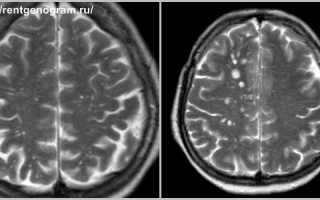

В норме криблюры настолько малы, что не видны на снимке МРТ. Однако бывают случаи, когда при обследовании определяются расширенные периваскулярные пространства. Что значит такой результат диагностики? Это говорит о том, что криблюры визуализируются во время проведения МРТ-обследования. Они выглядят на снимке, как пятна белого цвета.

При нарушении мозгового кровообращения криблюры расширяются. Поскольку они заполнены ликвором –спинно-мозговой жидкостью. В них содержится большое количество атомов водорода. И в этой области сигнал отклика будет высокой интенсивности, что видно на снимках как пятно белого цвета.

Обычно, демиелинизирующие очаги выглядят как множественные белые точки. Пациент может воспринять их за криблюры, потому что они похожи. Отличить их друг от друга может только специалист по степени выраженности и локализации повышенного сигнала.

Магнитно-резонансная томография выявляет структурные нарушения головного мозга.

Отличить снимок здорового головного мозга от снимка с патологическими очагами может любой человек. Но поставить диагноз сможет только врач после длительного изучения результатов МРТ.